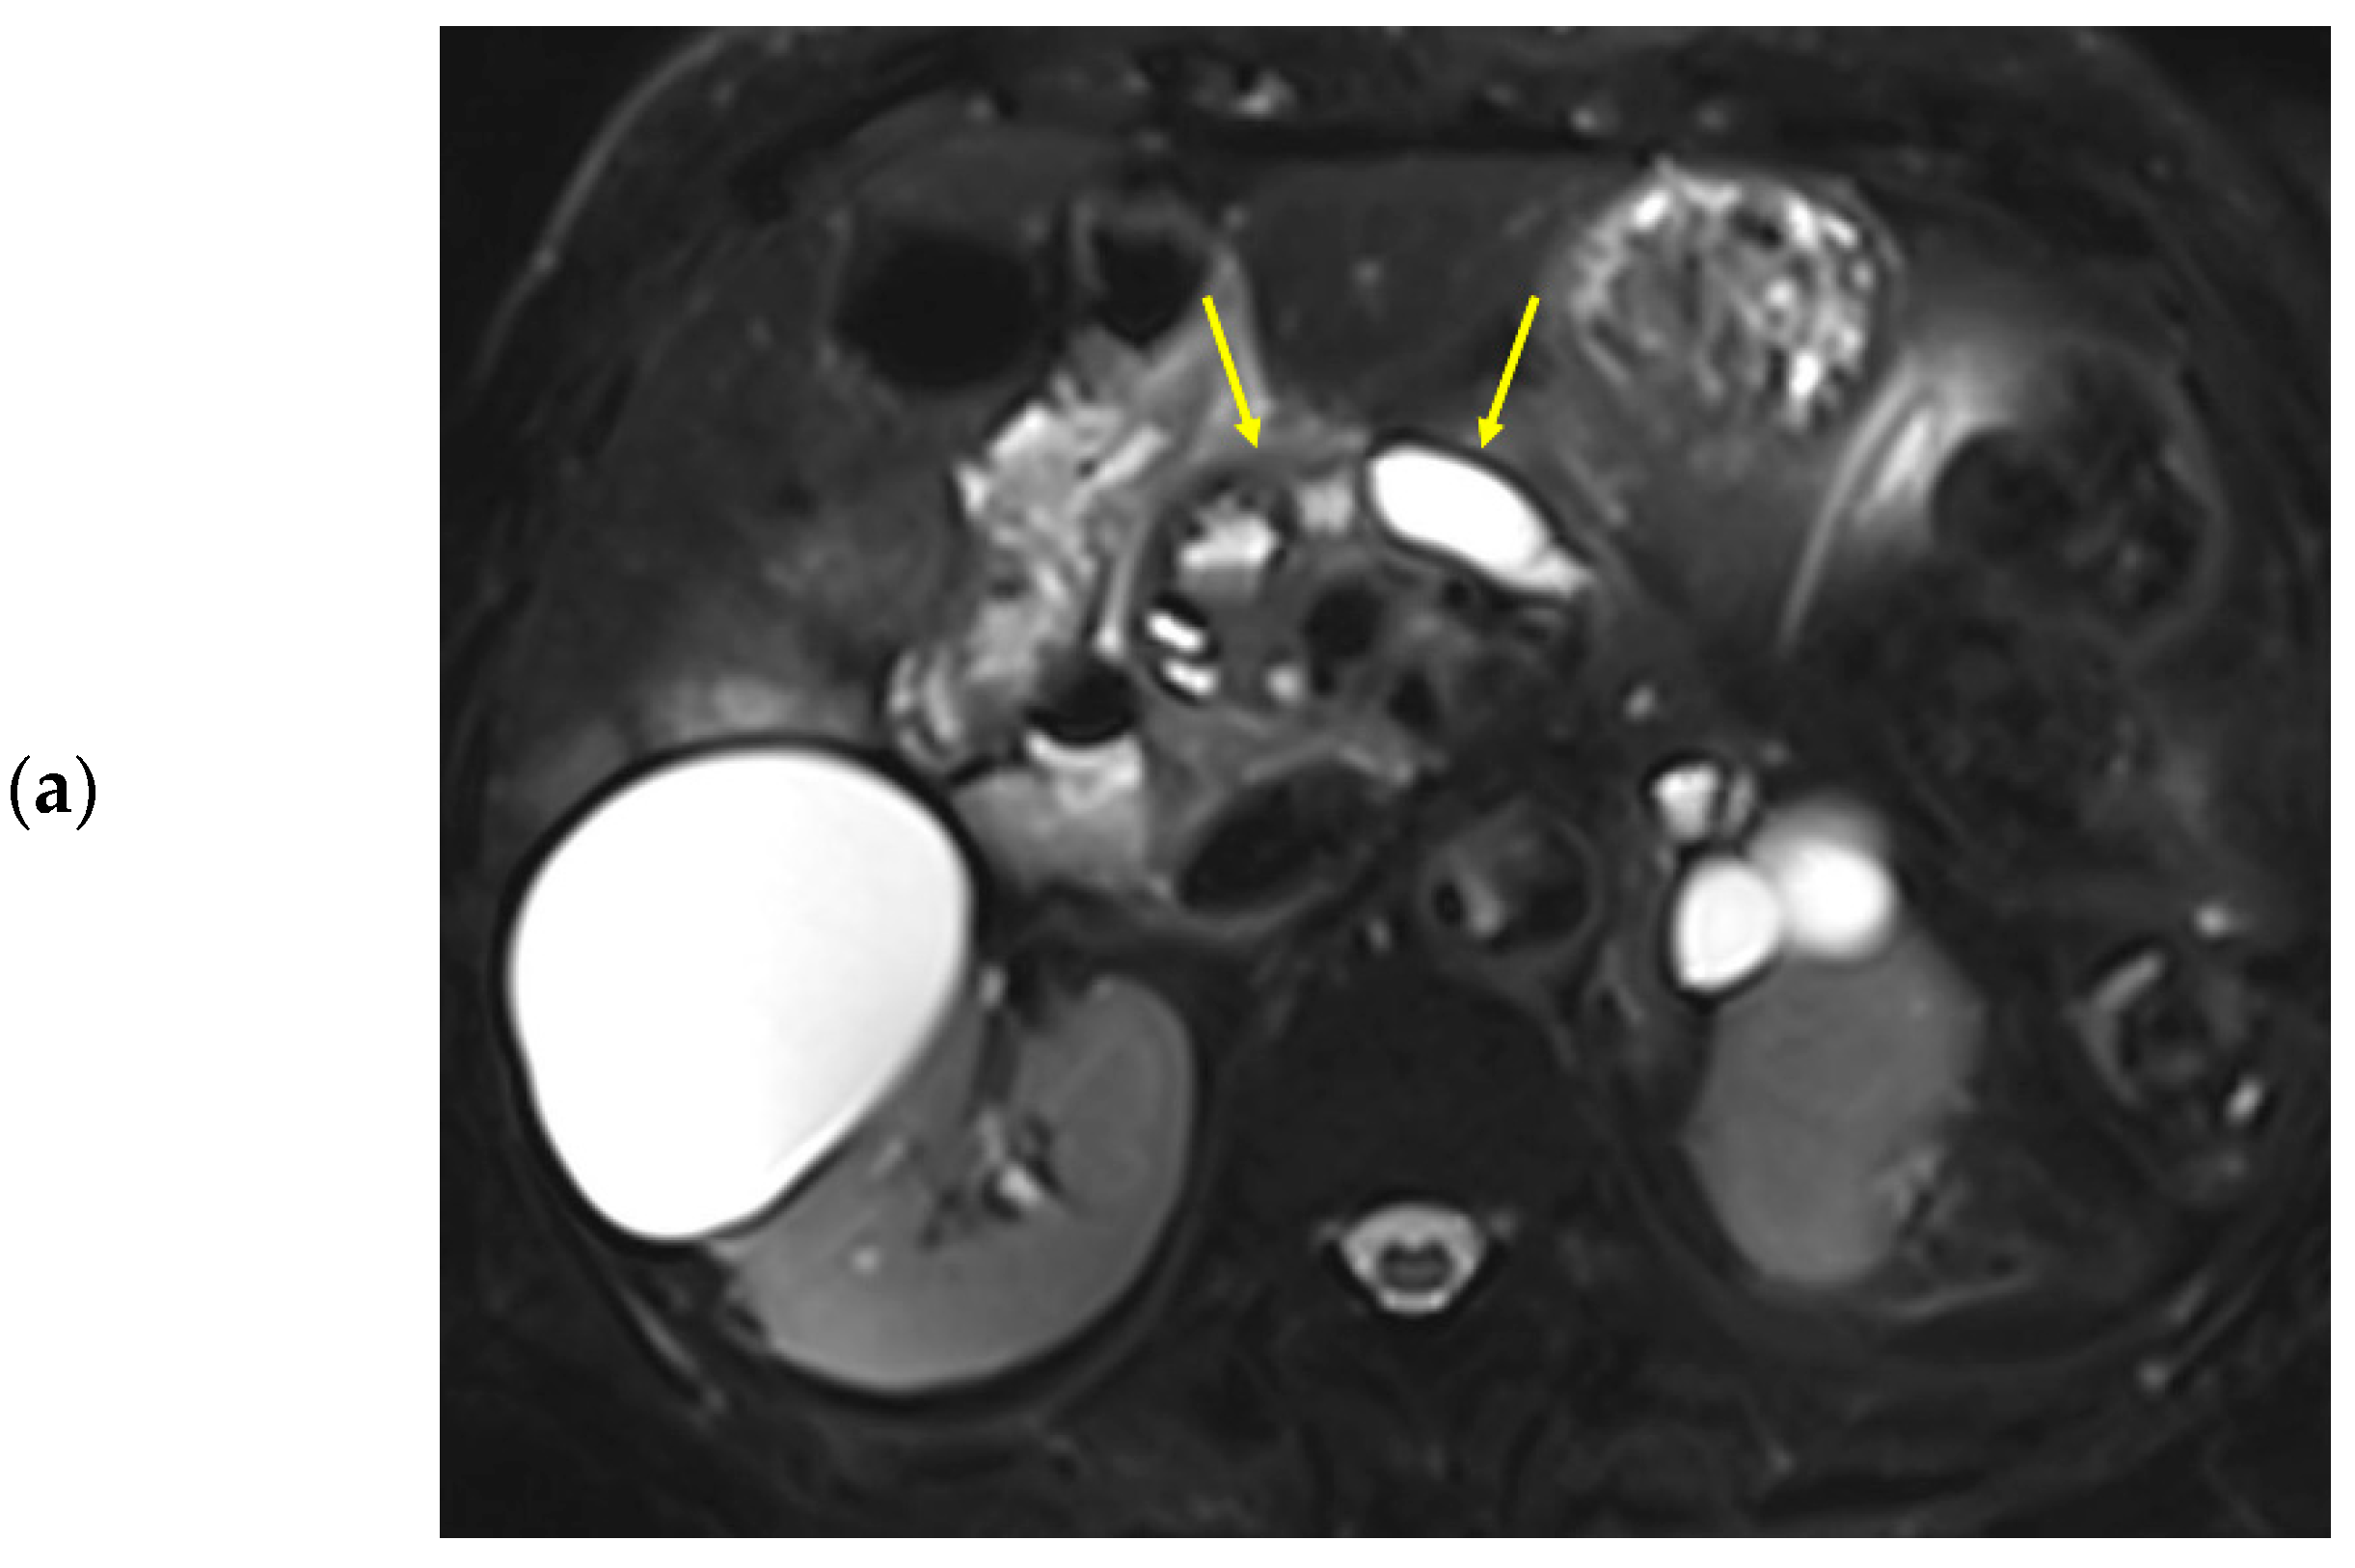

Figure 3. Eighty-nine-year-old female patient undergoing an MRI to evaluate pancreatic focal lesions. Diffuse pancreatic dilatation (arrows) is noted on T2-weighted imaging (a), and a 2.5 cm mass suspected to be pancreatic cancer is noted in the pancreatic head (not presented). Dynamic contrast-enhanced curves show gradual enhancement with stable signal intensity in the pancreas head, body, and tail (b).